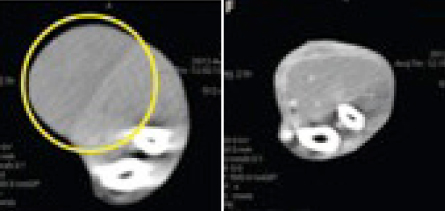

Proving there’s a time and place for everything, the research team, including scientists at BioMed Valley Discoveries in Kansas City, Mo., are genetically altering the microbe, removing the lethal-toxin gene. The new, nonlethal strain, called C. novyi-NT for “nontoxic,” still produces enzymes that eat proteins and lipids in cell membranes. The researchers have injected spores of C. novyi-NT directly into tumors of rodents, dogs and a woman whose advanced cancer had resisted all other treatments.

When injected, two things happened, as the team reported in the Aug. 13 Science Translational Medicine: The bacteria digested the tumor and the infection induced a powerful immune response, bringing the immune cells into the fight.

“This strong immune response, we believe, not only targets the bacteria, but it targets the cancer as well,” Zhou says. After the bacteria was injected into her shoulder, the patient regained use of her arm, which had become immobile. She also developed a fever, severe pain in the injection area and an abscess in the tumor that doctors had to drain. She died six months after treatment due to cancer that had not been treated with the experimental bacteria.